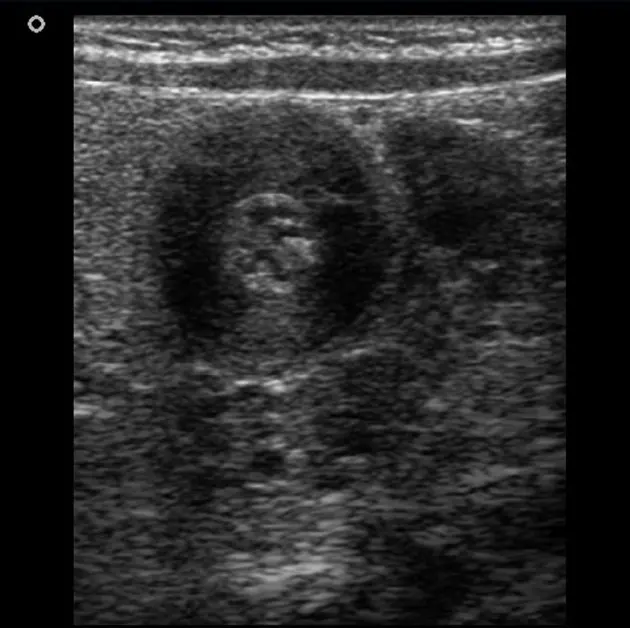

복부초음파 검사(DOC) : 날문부 근육층 4mm 이상, 날문부 길이가 15mm 이상 / Target sign

위장관 조영술 : 유문부 길이가 길어있음 확인